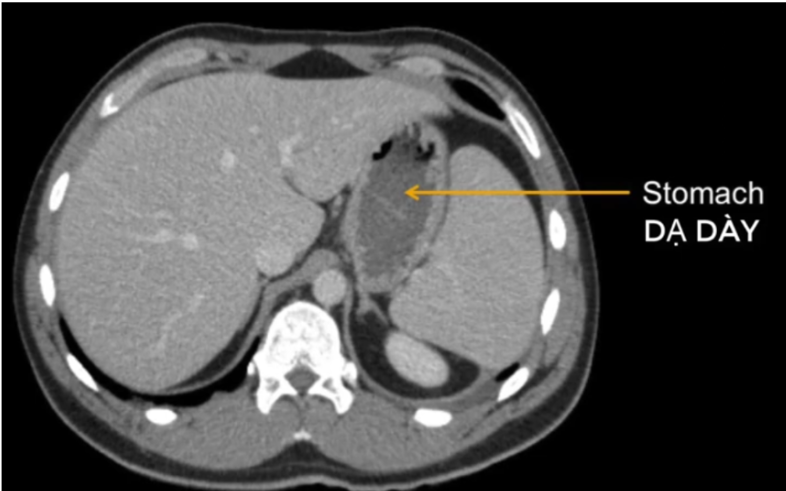

cq trong hình ?